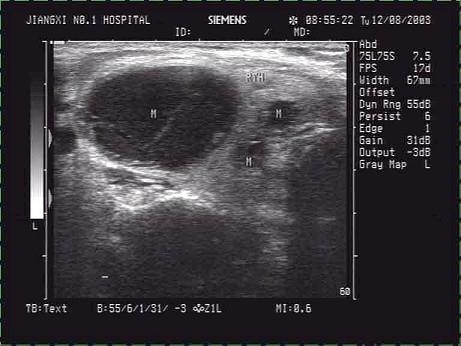

甲状腺超声声像图如下,最可能的诊断为?(?)A.甲状腺囊肿B.结节性甲状腺肿并囊变C.甲状腺腺瘤并囊变D.甲状腺囊腺癌E.甲状腺炎

问题 甲状腺超声声像图如下,最可能的诊断为?(?)

选项 A.甲状腺囊肿 B.结节性甲状腺肿并囊变 C.甲状腺腺瘤并囊变 D.甲状腺囊腺癌 E.甲状腺炎

答案 B